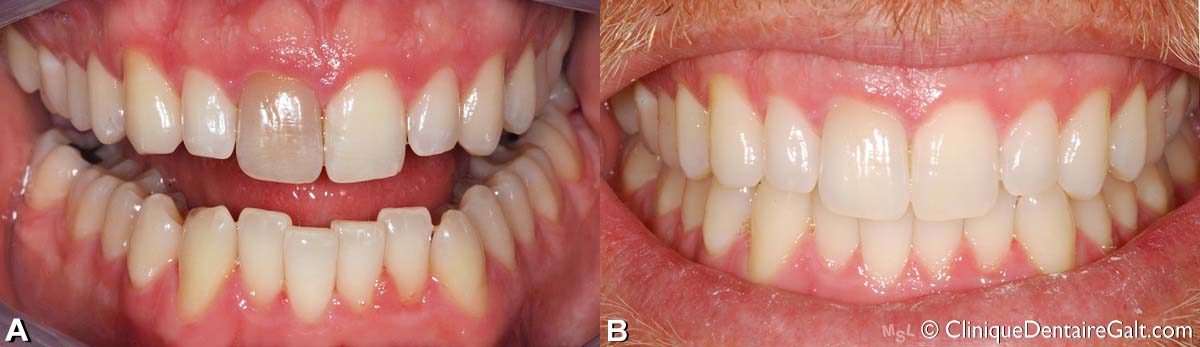

(A) Avant le traitement d’orthodontie, il y avait déjà eu un blanchiment. La position de la canine incluse est indiquée par l’astérisque bleu (*).

(B) Pendant le traitement , lorsque la canine sort et est tractée orthodontiquement, on remarque qu’elle est d’une couleur différente des autres dents blanchies.

(C) À la fin du traitement, cette canine qui n’a évidemment pas eu de traitement de blanchiment comme les autres dents, présente une couleur plus foncée.

(D) La patiente a donc fait blanchir cette canine qui est maintenant d’une couleur plus uniforme avec les autres dents.